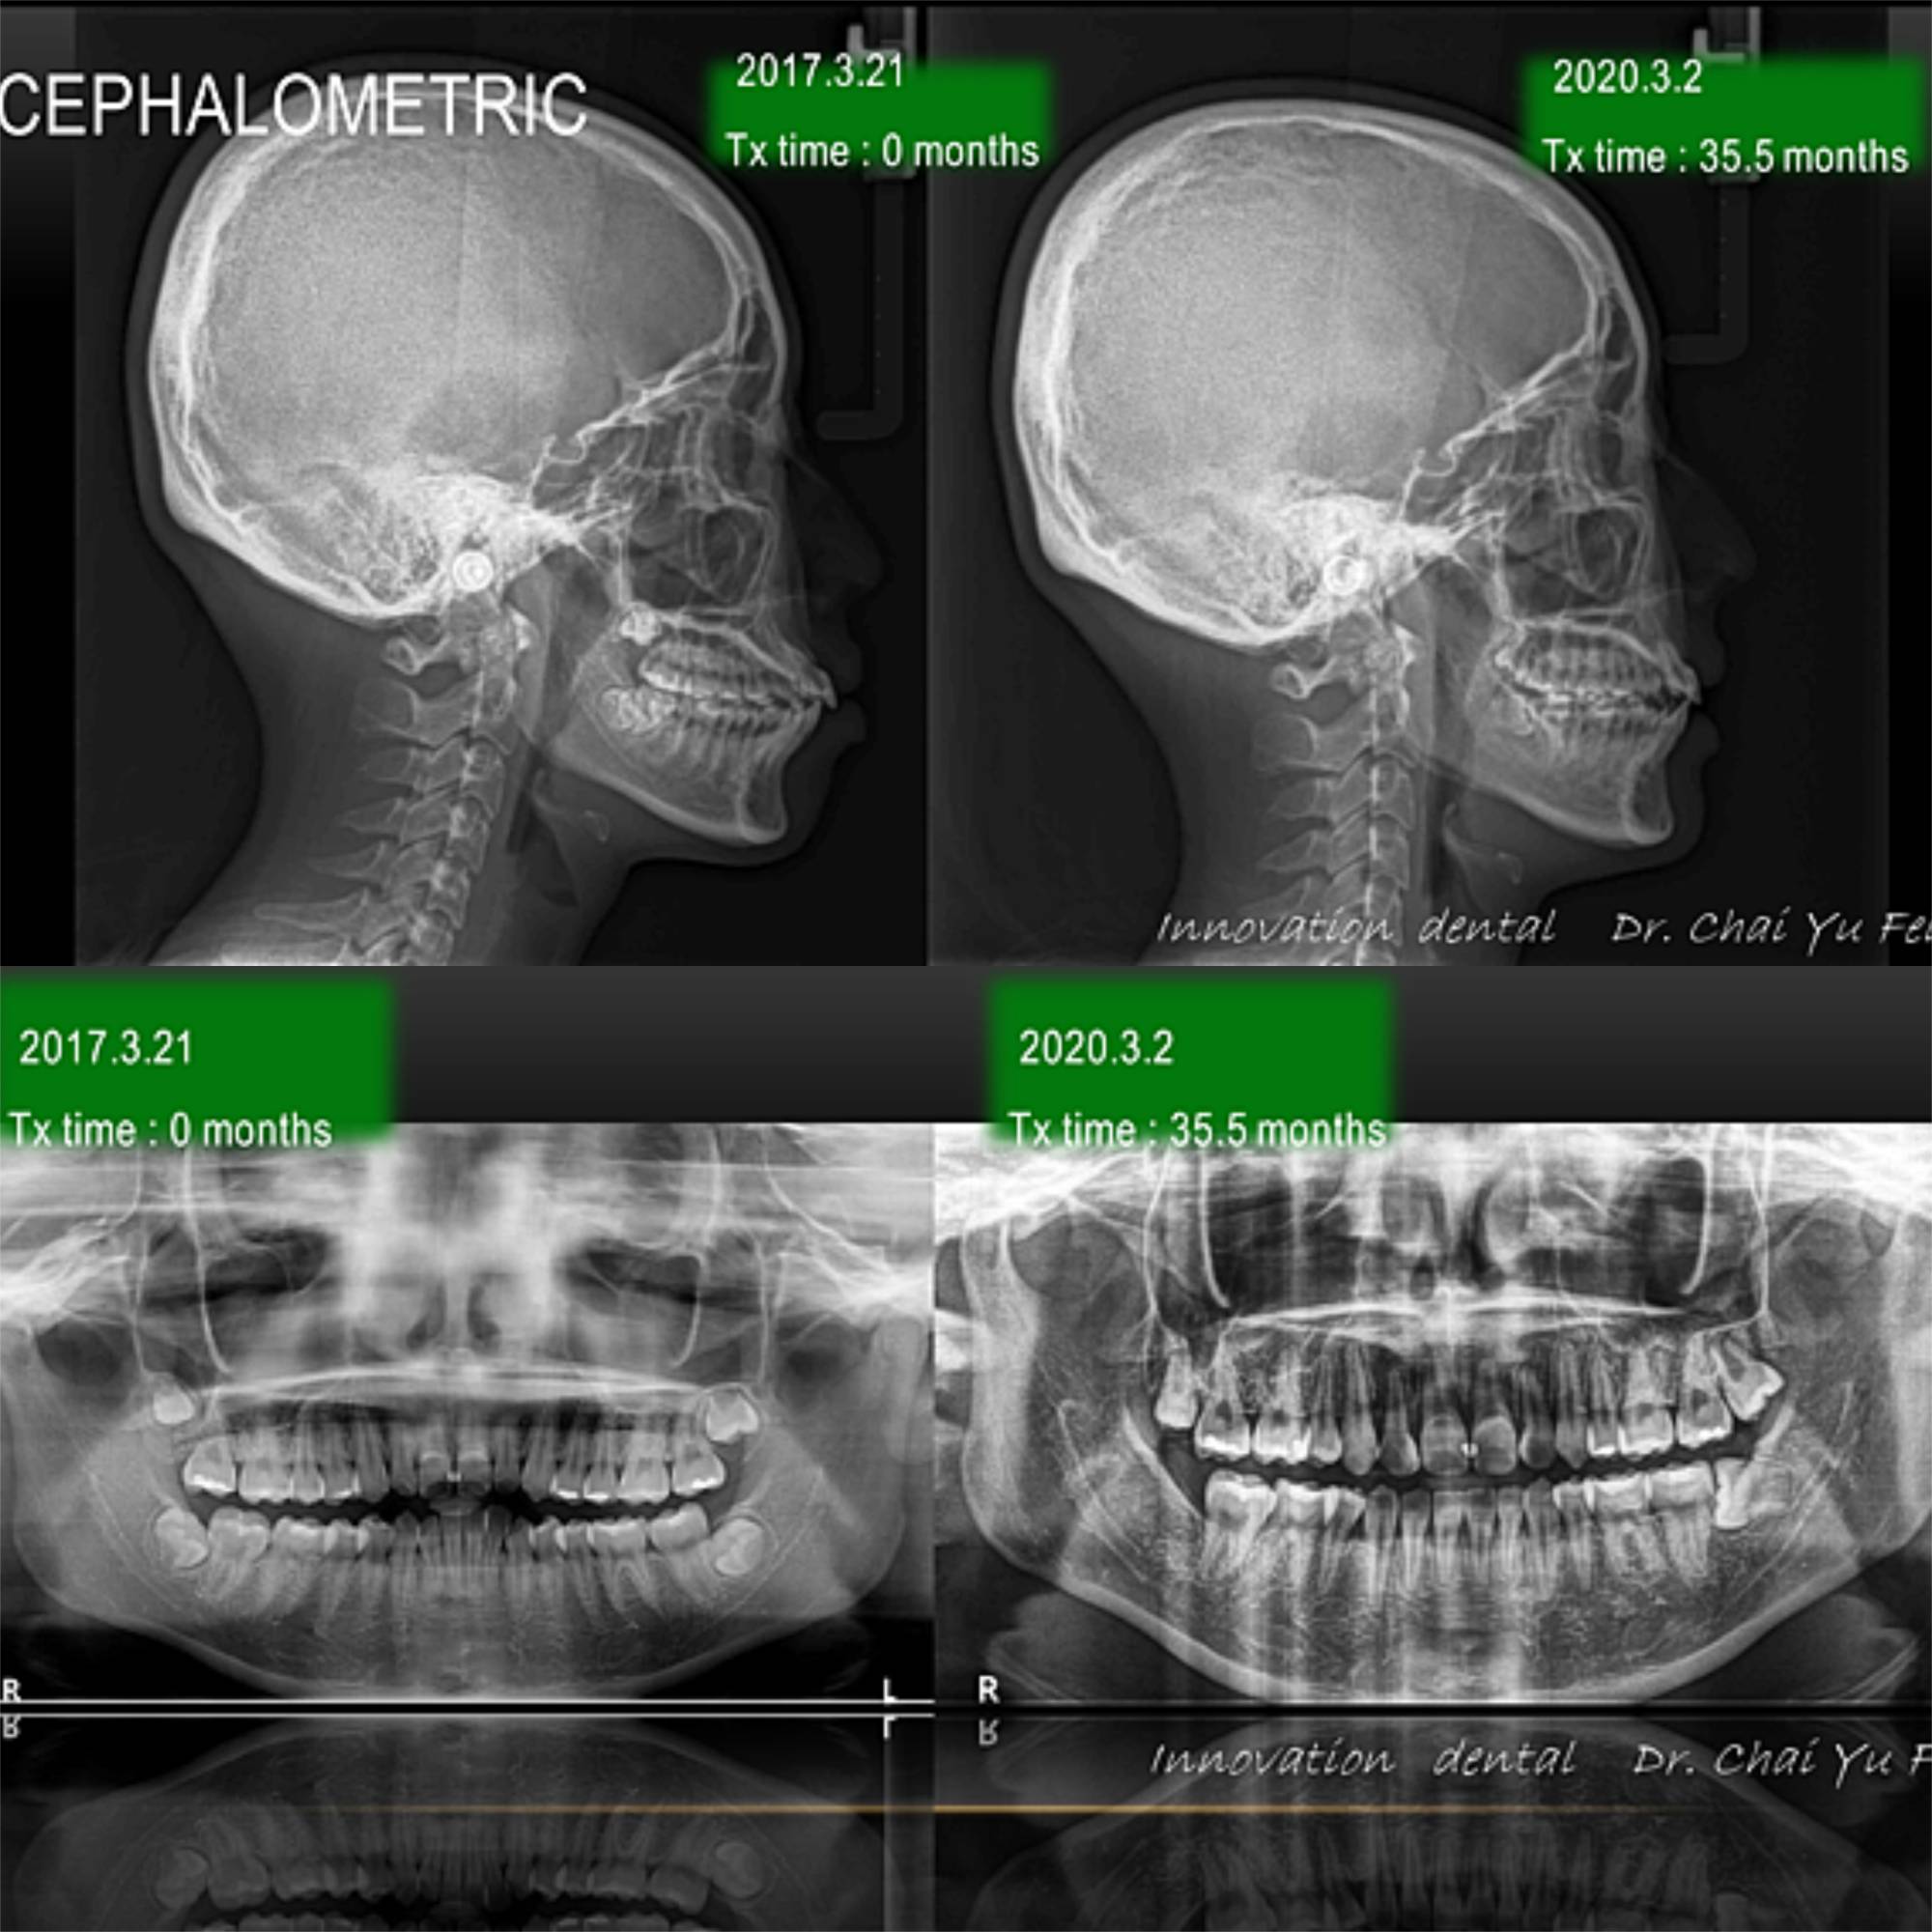

理想咬合可以靠拔牙與骨釘達成?外貌改善案例-H同學

[ 治療方式 ] : 拔牙矯正 ,利用拔牙空間將暴牙空間內收 ,改善原本嘴唇前突。

[ 治療時間 ] : 35.5 個月

上顎兩顆小臼齒的拔牙空間順利關閉。藉由骨釘後退達到理想咬合。下顎咬合平面整平後,再向內移動改善唇型。

▼ 治療前後の比較 (上顎・下顎)

治療後の写真です。治療前と比較すると、歯が歯列にそってアーチ状にキレイに並んでいるのがわかります。

歯の裏側が見えていた2本の前歯の傾斜も改善されているのがわかります。